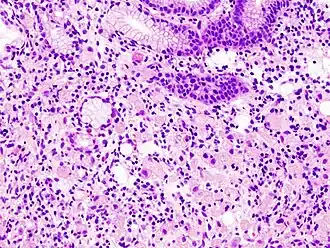

Gastric signet ring cell carcinoma. H&E stain. -